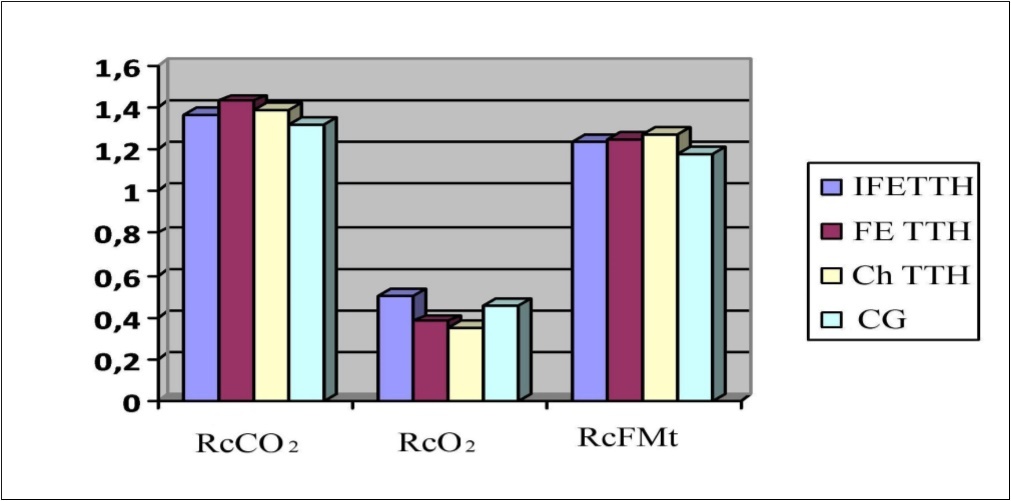

In patients with TTH, hyper-responsiveness to hypercapnic test was detected: RcCO2 was 1.43±0.05 in the group with FE TTH; 1.39±0.07 in the group of Ch TTH and 1.37±0.04 in the group of IFE TTH, which indicates a tendency for the tension of the vasodilator regulation mechanism even in clinically insignificant forms of TTH. In the study of reactivity to the O2-test, a hyporeactive response was observed in the groups with FE TTH and Ch TTH (0.38±0.04 and 0.35±0.05), respectively (Figure 3). As can be seen from Figure 3, in all groups, the reactivity coefficient (Rc) when performing functional tests using CO2 and FMt was significantly higher than using O2 (P <0.001).

Figure 3.Parameters of reactivity coefficient (Rc) to the CO2, O2 and FMt test in a patients with TTH.

In patients with IFE TTH the average value of RcFMt was 1.24±0.03, in patients with FE TTH - 1.25±0.02, in patients with Ch TTH - 1.27±0.03. In patients with TTH, hyper-responsiveness to hypercapnic test was detected: RcCO2 was 1.43±0.05 in the group with FE TTH; 1.39±0.07 in the group of Ch TTH and 1.37±0.04 in the group of IFE TTH, which indicates a tendency for the tension of the vasodilator regulation mechanism even in clinically insignificant forms of TTH. In the study of reactivity to the O2-test, a hyporeactive response was observed in the groups with FE TTH and Ch TTH (0.38±0.04 and 0.35±0.05, respectively.